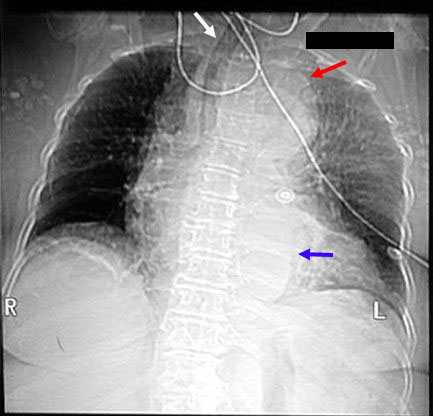

Radiologic Criteria for dissection in plain chest radiograph:

• Demonstrates mediastinal widening in around 63% of patients with an aortic dissection, however this finding is nonspecific and is seen in many normal age-matched controls.

• Internal displacement of aortic calcifications by 1 cm or more and disparity in size between the ascending and descending aorta are more specific for aortic dissection, especially when they represent a new finding compared to old films.

• Inlet to outlet shadow with wavy margins

• Frequently a left pleural effusion is seen.

• Localizes bulging of the aortic contour indicating the likely site of origin of a dissection.

Aortic Dissection CXR

Widened mediastinum

Inlet to outlet shadow on left with wavy margin